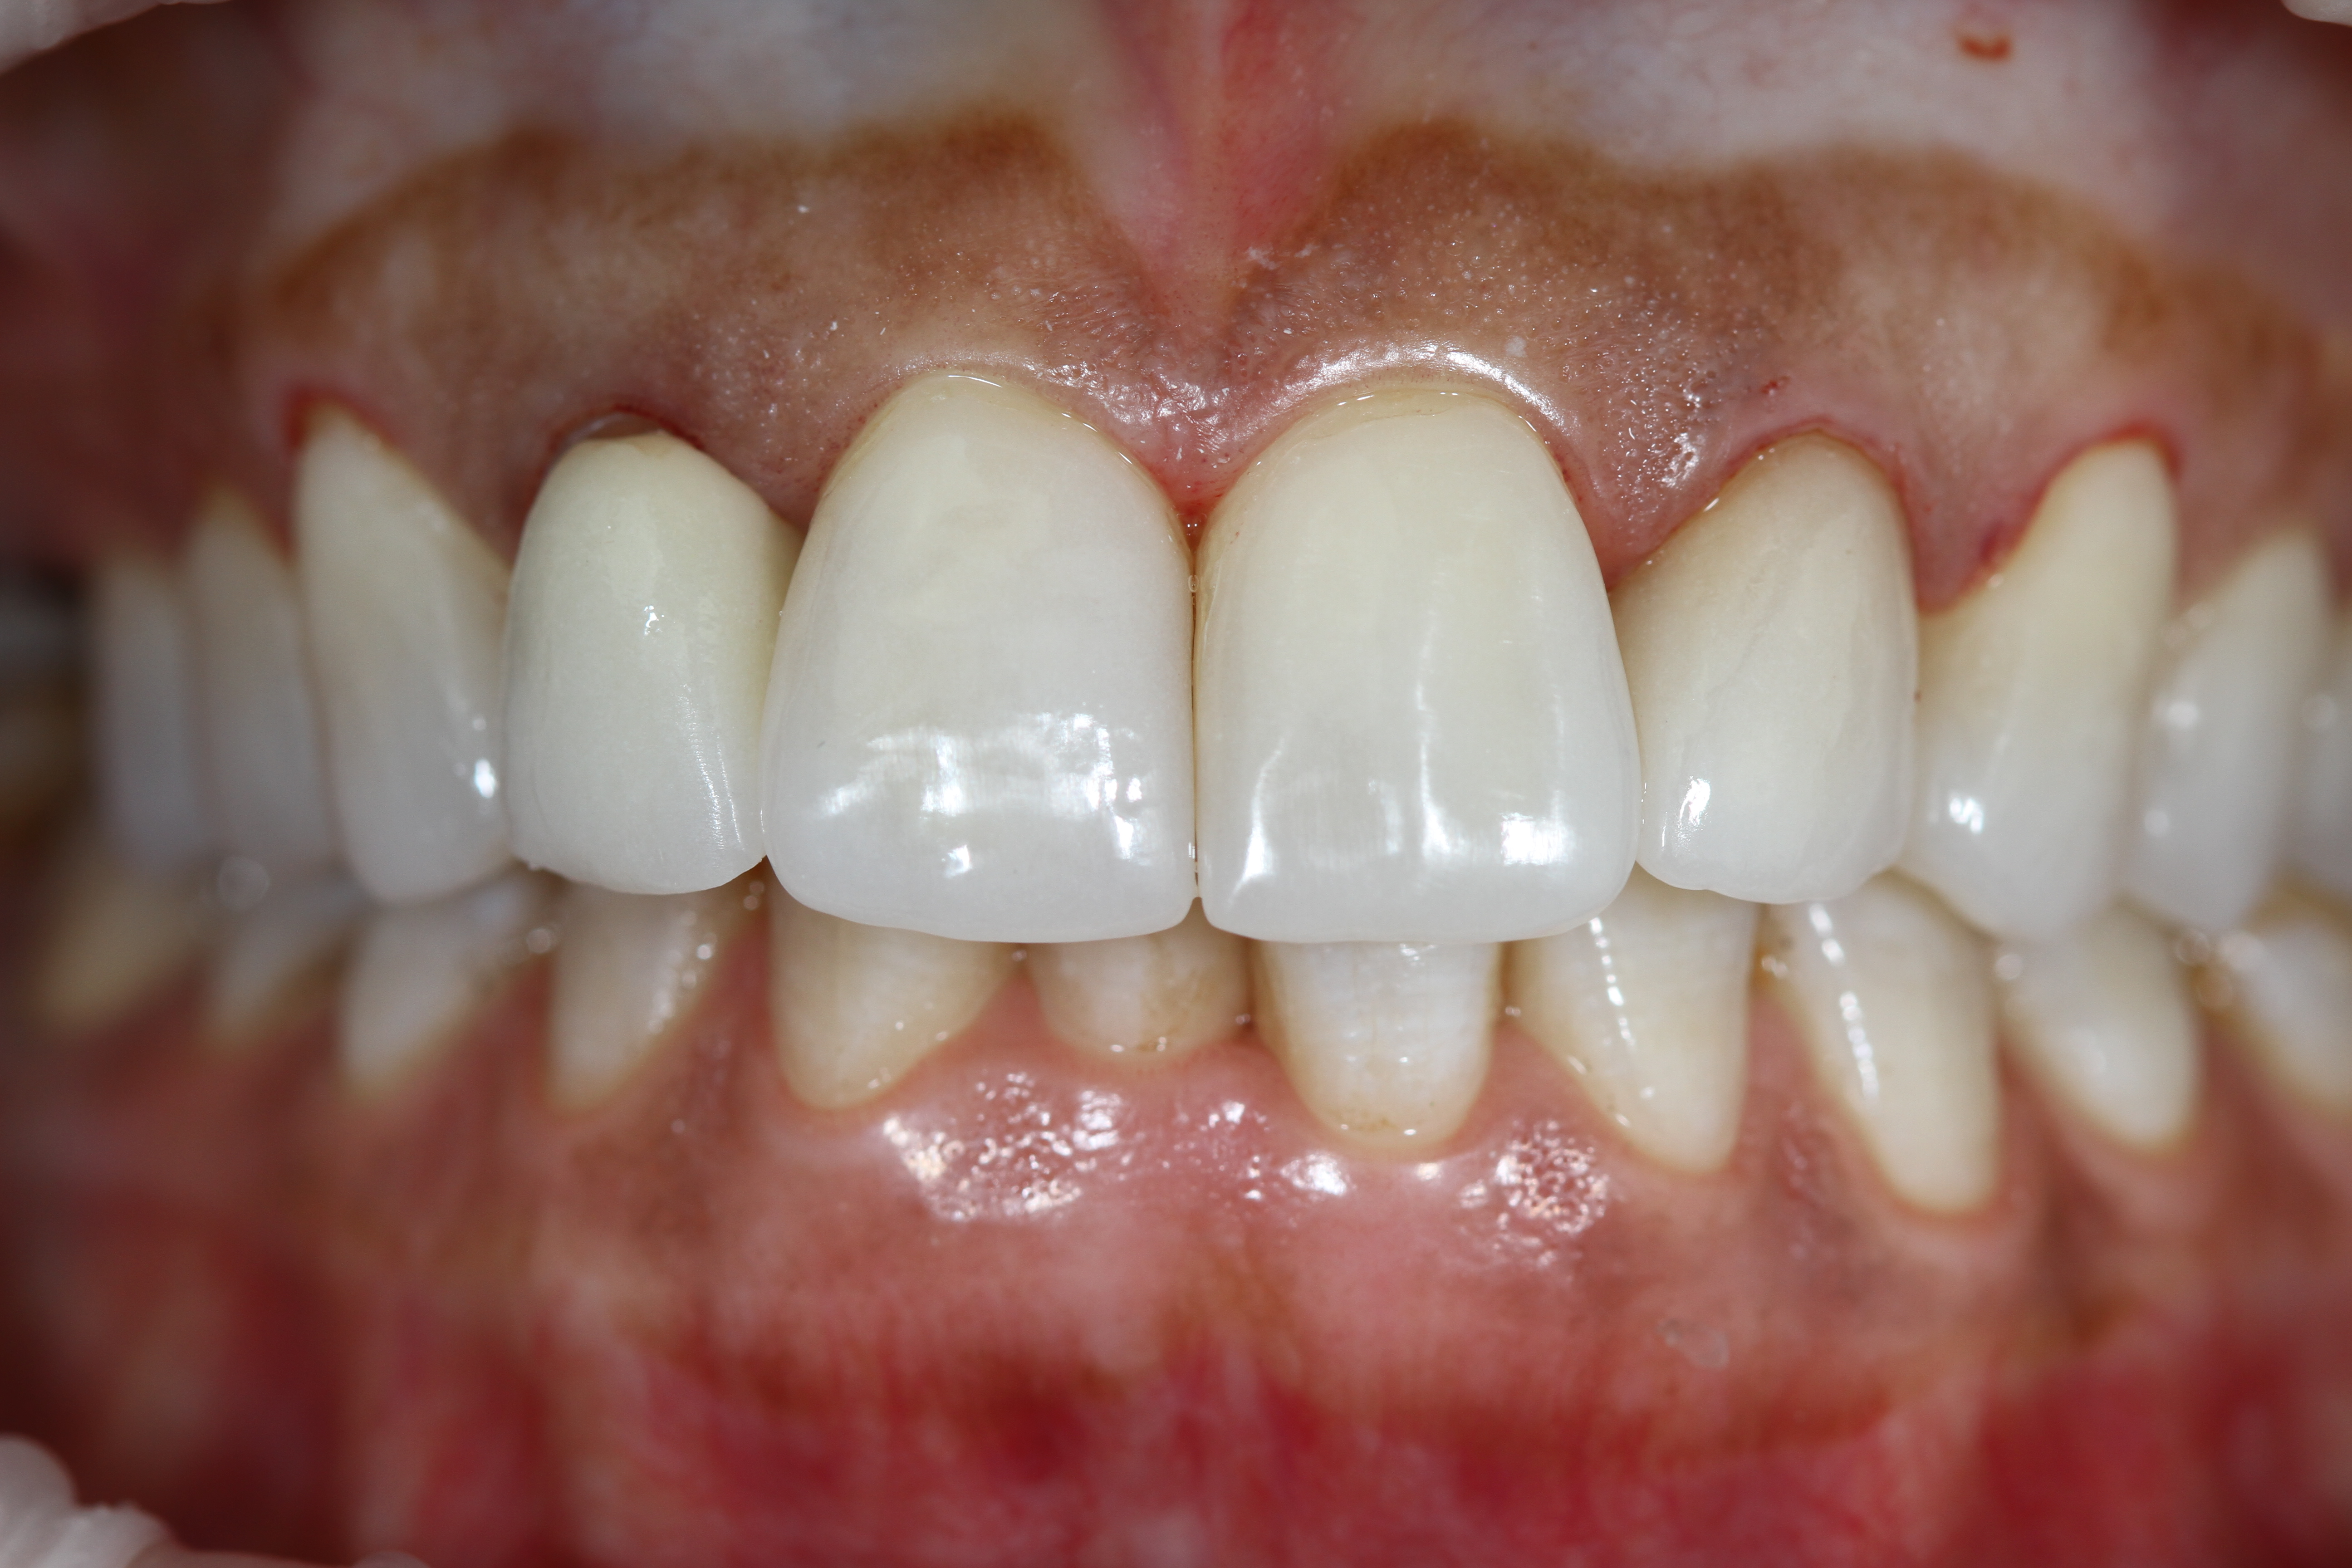

Белые виниры BLEACH

Все чаще стали поступать заказы на виниры цвета BLEACH. Очень красивый результат. Улыбка становится очень красивой.

Это виниры на рефракторе . 12 зуб коронка на оксиде циркония.